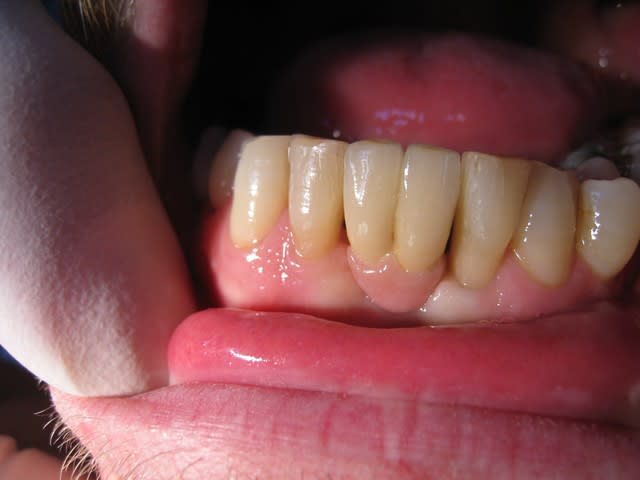

Hello

Un compromis pour remplacer 2 centrales 31-41

Voilà c'est mon 1er post !!

Donc je pensais à un système prothétique avec fausse gencive, soit transvissé ou scellé ! J'ai choisi scellé à cause de l'éventuelle sortie de vis.

Un pilier Procéra titane et un ensemble CCM avec céramique rose autorisant le passage du fil dentaire.

Sans cette fausse gencive, comment gérer les positions médiane et basse de l'implant/pilier proth. ?

Il est vrai que pour l'hygiène, c'est délicat ! Mais comme pour beaucoup de cas il faut voir à 6 mois et plus si affinités !! J'attends de revoir